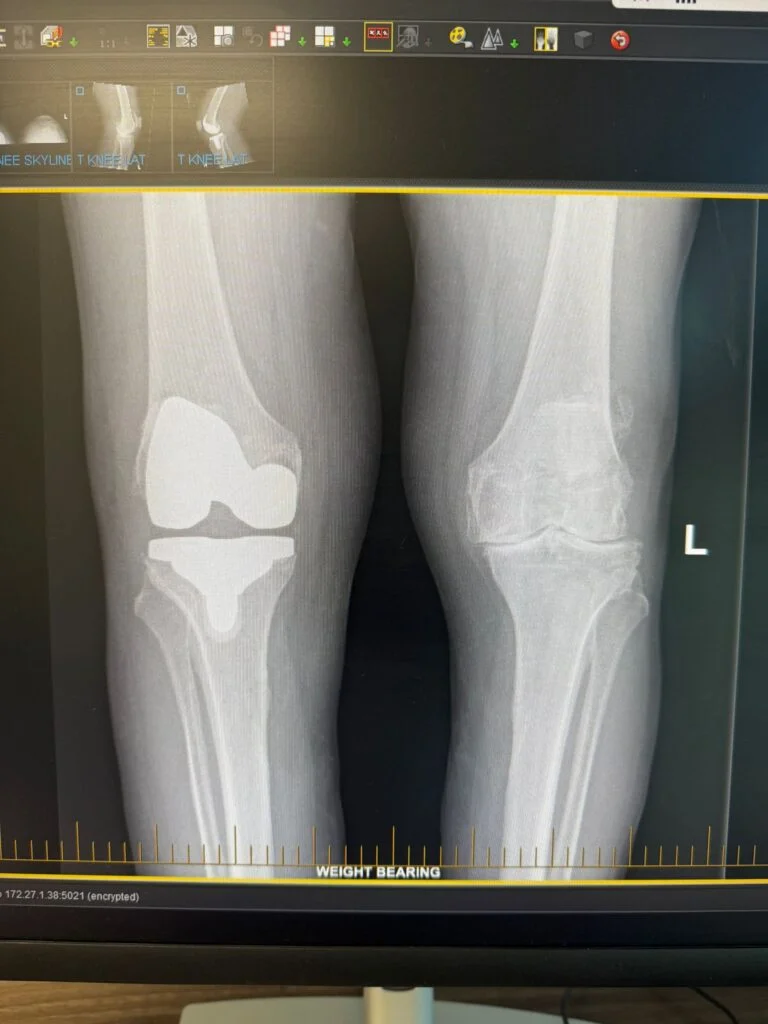

• Partial Knee Replacement Surgery

• Robotic Knee Replacement Surgery

Partial Knee Replacement

Total Knee Replacement

Robotic Knee Replacement